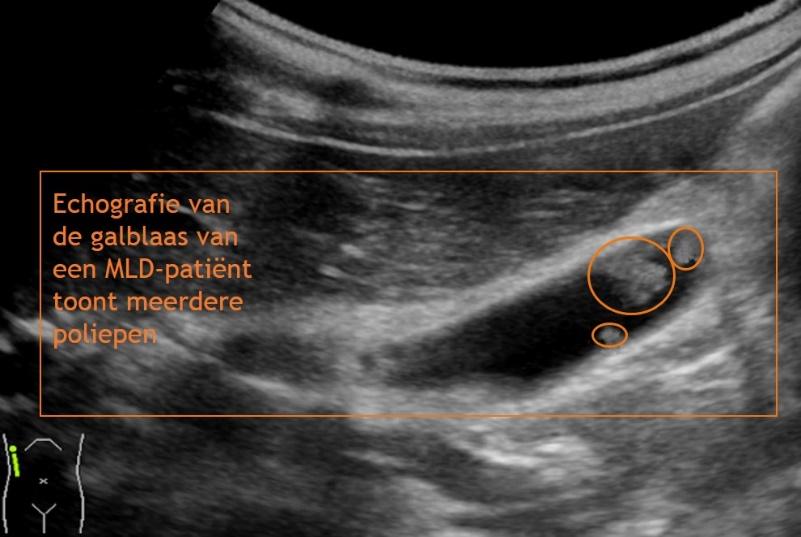

Echografie van de galblaas

MLD-patiënten hebben een grotere kans op het ontwikkelen van galstenen, een ontsteking van de galblaas of poliepen in de galblaas. Dit kan leiden tot buikpijnklachten, meestal rechts in de bovenbuik. Daarnaast geeft dit een hogere kans op galblaaskanker. Met behulp van echografie wordt gekeken of er sprake is van één of meerdere van deze galblaasproblemen. Indien dit het geval is, wordt geadviseerd de galblaas door middel van een kijkoperatie te verwijderen.